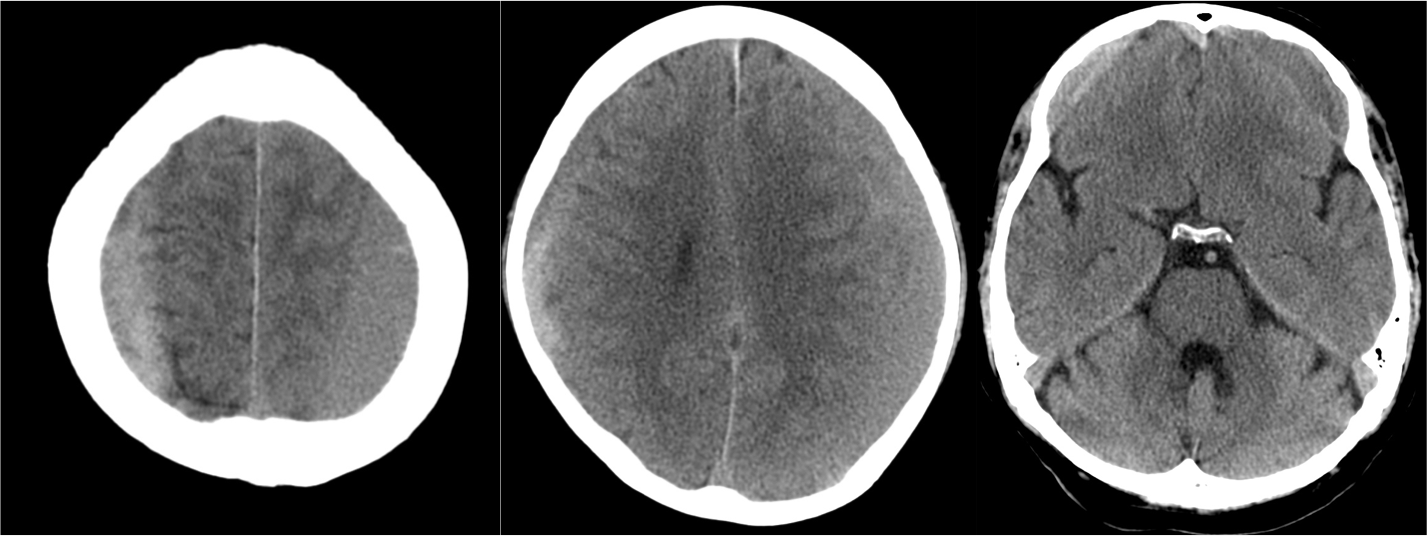

Hallazgos TC:

- En fase aguda puede ser Nomal.

- Edema cerebral (borramiento de surcos)

- Focos hemorrágicos en las sitios anteriomente descritos

- En fase cronica = zonas hipodensas + atrofia.

1- Edema cerebral difuso: Aparece en las primeras 48 horas del traumatismo. Se identifica por:

- Produce efecto de masa.

- Borramiento de surcos = pérdida de la interfase sustancia gris-sustancia blanca.